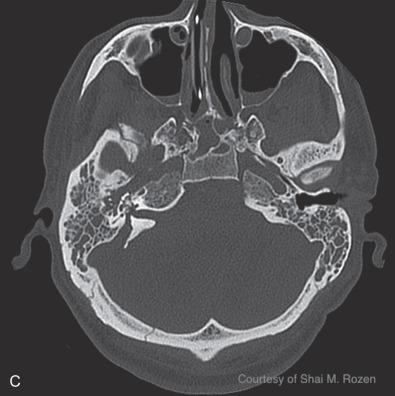

Temporal bone fractures are a product of high-energy blunt trauma commonly resulting in fracture, hemorrhage, nerve trauma, vascular damage, with disruption of the middle or inner ear structures, classically classified into longitudinal, transverse, or oblique fractures. Longitudinal fractures often result from lateral to medial forces extending through the facial nerve canal, possibly causing intraneural hemorrhage, transection, or bone compression. They can disrupt the ossicular chain, resulting in conductive hearing loss. Transverse fractures often result from anterior posterior forces with a fracture line often traversing the vestibulocochlear apparatus causing sensorineural hearing loss and equilibrium disorders. Transverse fractures more commonly injure the facial nerve due to proximity to the nerve’s labyrinthine segment. Oblique, also termed mixed, fractures include both longitudinal and transverse components. Additional classifications are based on degree of involvement of the petrous portion of the temporal bone, or the otic capsule. Temporal bone computed tomography (CT) scans should be performed in thin-section 1 mm cuts to avoid interpreting normal suture lines as fractures.

Blunt injuries resulting in temporal bone fractures are often encountered in motor vehicle accidents, altercations, or falls from heights. Approximately 7%–10% of temporal bone fractures result in facial nerve injury. Temporal bone fractures have several classifications. Fracture line orientation relative to the petrous bone defines fractures as longitudinal (70%–80%), transverse (10%–20%), and oblique (10%). Facial paralysis occurs most commonly in transverse fractures (50%) but may also occur in longitudinal fractures (25%). More modern CT-based classifications assess whether fractures are otic capsule sparing or violating, the latter being twice as likely to cause facial paralysis. Four types of facial nerve trauma have been found in temporal bone fractures. In 76% of longitudinal fractures either bony impingement or intraneural hematoma was found, and in 15% the nerve was transected. In the remainder of patients, no visible pathology was found other than neural edema. In transverse fractures, 92% were transected and 8% had impingement ( Fig. 1.5.3 ). Similar to penetrating intracranial facial nerve injuries, surviving patients are initially often in critical condition and the facial paralysis is often unnoticed.